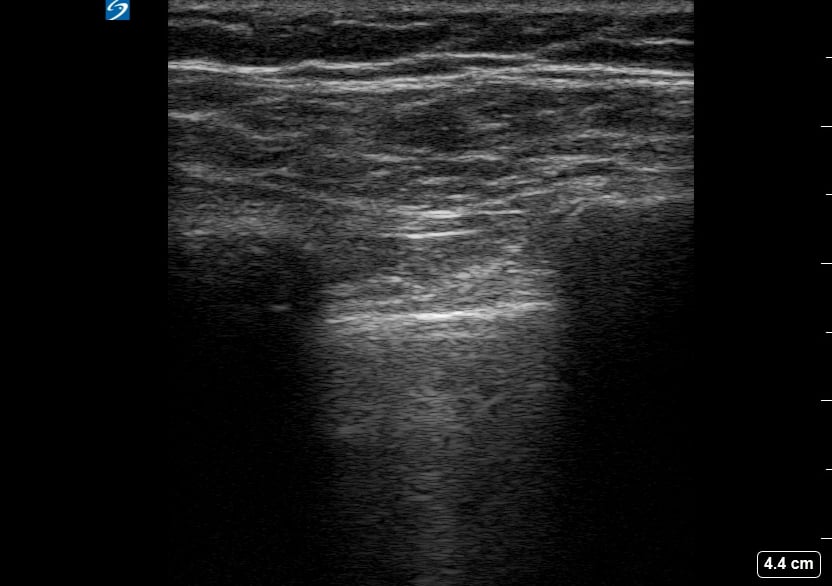

Pneumothorax

A pneumothorax, or collapsed lung, occurs when air leaks into the space between the lung and chest wall, causing the lung to partially or completely deflate. In a medical setting, prompt diagnosis is crucial to prevent respiratory distress. Ultrasound is a valuable tool for quick assessment, revealing characteristic signs like the absence of lung sliding or the presence of a “barcode” or “stratosphere” sign in M-mode, aiding rapid clinical decisions.

Ultrasound imaging for pneumothorax offers a non-invasive, real-time method for detection, especially in emergency and critical care. Key ultrasound findings guide clinicians in identifying this potentially life-threatening condition, facilitating timely intervention and improved patient outcomes. Understanding these signs is essential for medical professionals utilizing point-of-care ultrasound for lung pathology.